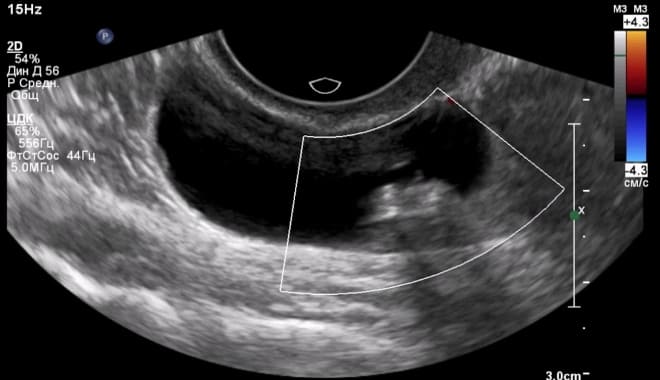

Как выглядит киста яичника на УЗИ

В гинекологии киста представляет собой полую опухоль, чаще всего доброкачественного характера, заполненную жидкостью.

Главным признаком кисты яичника при ультразвуковом исследовании является образование полого отростка на его поверхности. В отличие от нормального фолликула, который изменяется в течение менструального цикла, киста остается неизменной. Кроме того, такое образование обычно имеет больший размер.

На ультразвуковом снимке киста яичника отображается в виде черного пятна, размеры которого варьируются от 3 до 20 см.